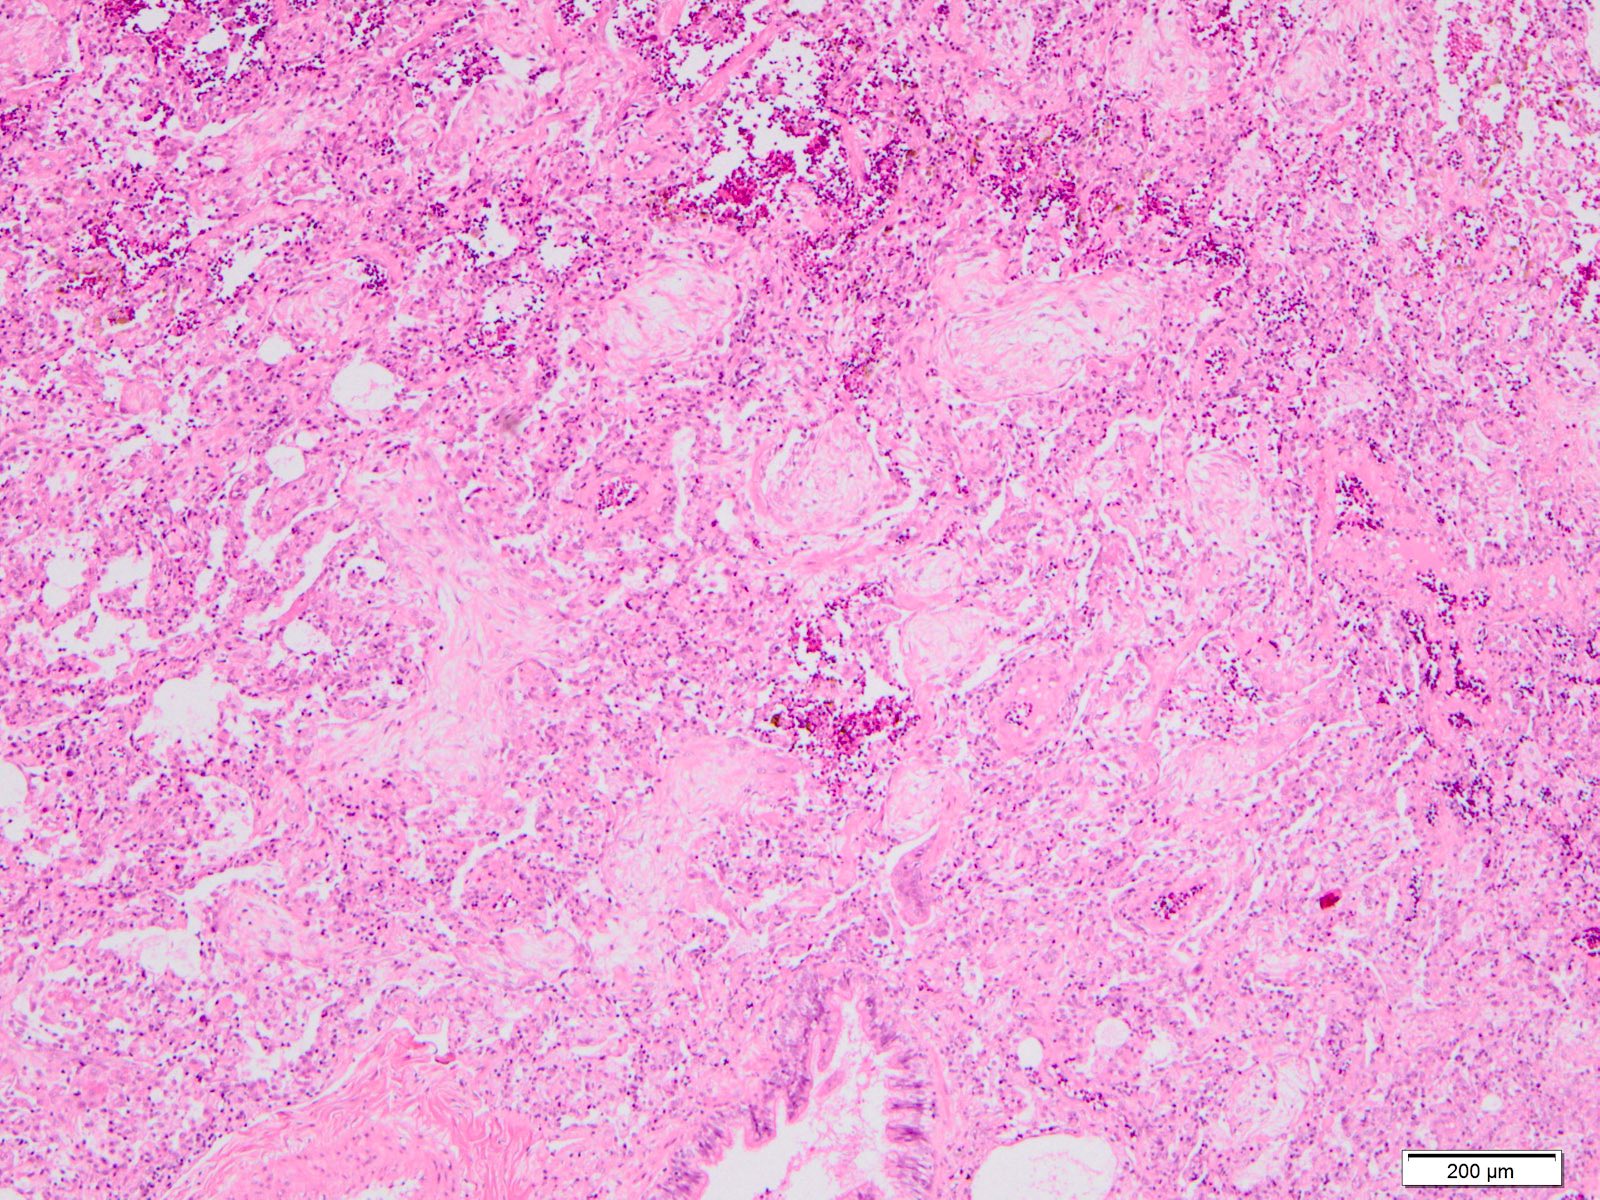

Microscopic (histologic) description

- Histopathology of DAD progresses from exudative (acute) phase through proliferative / organizing (subacute) phase to chronic fibrotic phase roughly corresponding to the period of ARDS (Am J Pathol 1976;85:209, Arch Pathol Lab Med 2010;134:719, Clin Chest Med 2000;21:435, N Engl J Med 2000;342:1334)

- Exudative (acute) phase

- Proliferative / organizing (subacute) phase

- Alveolar change

- Remnants of hyaline membrane with or without organization

- Interstitial and intra-alveolar proliferation of myofibroblasts

- Lymphocytic infiltration

- Epithelial change

- Proliferation / hyperplasia of type II pneumocytes

- Vascular change

- Endothelial injury and thromboemboli in arterioles

- Alveolar change

Microscopic (histologic) images

Contributed by Akira Yoshikawa, M.D. and Yale Rosen, M.D.